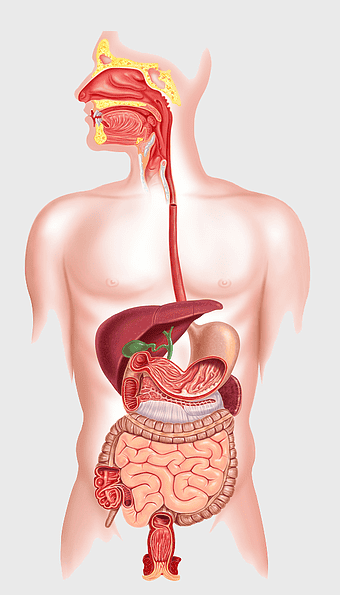

human gastrointestinal tract anatomy, human digestive system illustration, gastrointestinal disease symptoms, human body organ diagram, internal organ visualization, medical anatomy study, digestive health awareness -

Crohn's disease illustration, gastrointestinal tract diagram, large intestine anatomy, digestive system cartoon, medical illustration, human anatomy study, chronic inflammatory bowel condition -

human digestive system, gastrointestinal tract anatomy, liver function, stomach and intestines, digestive health, internal organs diagram, human body systems -

Gastrointestinal tract anatomy, Stomach health, Crohn's disease symptoms, Digestive system, Intestinal inflammation, Human anatomy illustration, Medical diagram -

digestive system diagram, gastrointestinal tract chart, human anatomy illustration, small intestine function, digestive process visualization, internal organ layout, metabolic system overview -

human digestive system illustration, gastrointestinal tract diagram, human body organ system, labeled digestive system, digestive anatomy chart, human internal organs, alimentary canal visualization -

Gastrointestinal tract diagram, Small intestine anatomy, Large intestine function, Apparato digerente illustration, Digestive system structure, Intestinal health, Human anatomy organs -

human stomach anatomy, gastrointestinal tract illustration, small intestine diagram, peptic ulcer disease, digestive system health, internal organ function, pink medical graphic -

Gastrointestinal tract illustration, leaky gut syndrome symptoms, small intestine diagram, large intestine function, digestive system health, human anatomy chart, internal organ visualization -